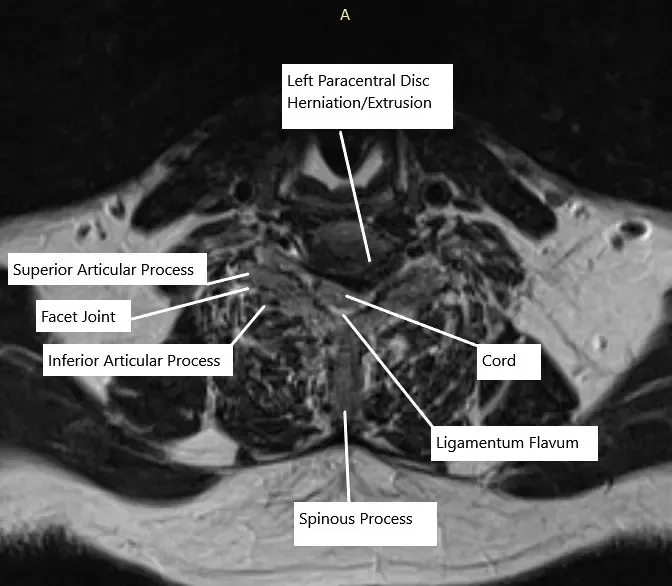

En C6-C7, hay una hernia/extrusión del disco paracentral izquierdo que crea una impresión en la parte ventral del saco tecal y la médula espinal. Hay estenosis grave asociada del canal espinal y hipertrofia bilateral de la articulación uncovertebral. Existe una estenosis foraminal neural del lado izquierdo severa.

Resonancia magnética de la columna cervical a nivel C6-C7 en sección axial.